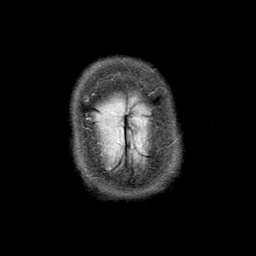

Pick's Disease, MR Study mr-t2 -- Slice #22

[Home][Help][Clinical] Slice 22